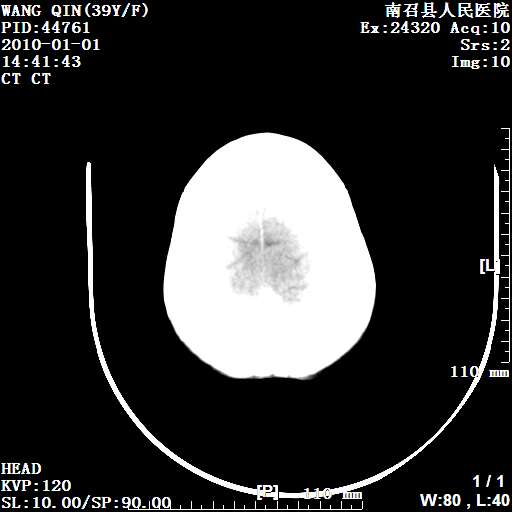

以下是引用随光逐影在2010-1-22 9:03:00的发言:[br]考虑左侧中颅窝(蝶骨翼区)脑膜瘤侵犯蝶骨翼并突入左侧眼眶。

以下是引用水过无痕在2010-1-22 14:55:00的发言:[br]一、定位:颅外占位;二、定性:恶性可能性大;三、组织来源:来源于左侧眼外直肌或其他部位;考虑为:横纹肌肉瘤>转移瘤>脑膜瘤.